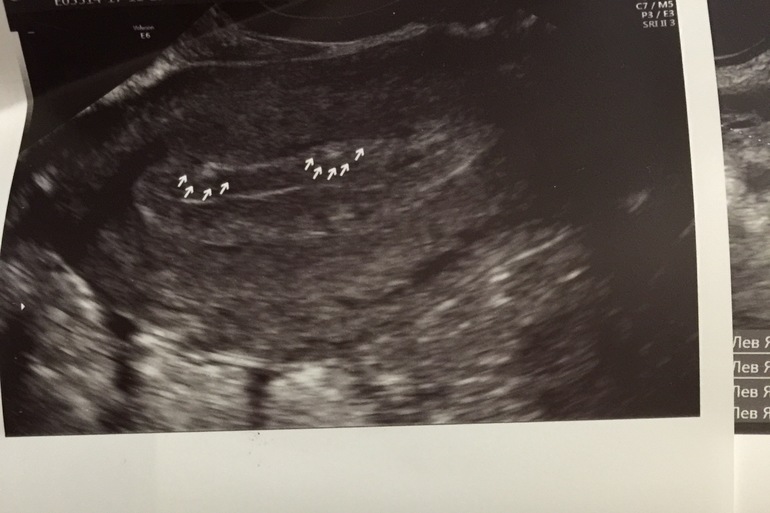

ГистероскопияДевочки, помогите разобраться, нужна ли гистера? Планируем 5 циклов, цикл четкий, никаких мажущих выделений нет и не было, была много раз на узи в Цире, отслеживала О, она есть, решила сходить к П*тых на экспертное узи, на 9 дц, сказала, что есть подозрение на формирующуюся ножку полипа, но это не точно, видны белые полосочки, сама видела на экране. На 14 дц с доплером сказала тоже самое, полипов не видно, но есть эти белые полосочки и кровоток, в центре где они, хуже. Заключение на фото. Девочки, может у кого-то было подобная ситуация, как считаете, делать ли гистеру? Г. сказал, вот будет полип, тогда и надо удалять, а так, на узи могло померещиться, если из-за каждого подозрения операцию делать...И тут читаю, часто на гистере не подтверждается увиденное на узи. И порекомендуйте пожалуйста, где можно сделать в Москве, проверенное место.